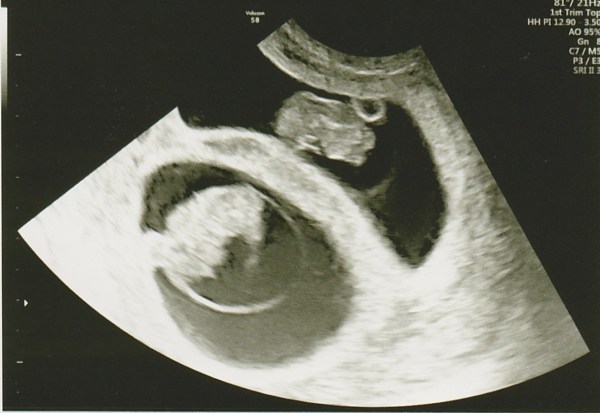

12 Week Scan

Today I had my 12 week scan, and I was so nervous. Apart from the morning sickness I had had no other clue that my babies were still ok since the 8 week scan. I sat in the waiting room unable to imagine past laying on the table and checking they were both ok.

The sonographer called us in and the first thing she said was ‘So you’ve got twins in there’ and being the negative nancy I was feeling that day I replied ‘Well I did at 8 weeks!’ and I think she understood that I wouldn’t relax until I saw them again so I lay down, and was holding my breath waiting to hear what she could see. TWO HEARTBEATS. They had both held on!

The scan was amazing and so clear. I have one on the left of my stomach and one on the right, with one anterior and one posterior placenta.

I got to see their tiny hands and feet wiggling around and how they were laying. It was amazing and made it all feel so much more real.

The left twin is minimally larger than the right one but both are totally on track for a 22nd September due date.

She struggled a bit to get the measurements for the Nuchal Translucency test, but she did manage in the end. One twin had a slightly larger measurement than the other, but all I can do now is wait for the letter in  the post with the results.

EDIT: The results came back extremely low risk for both (though one was 10,000 less likely than the other, with no indication as to which was which!)